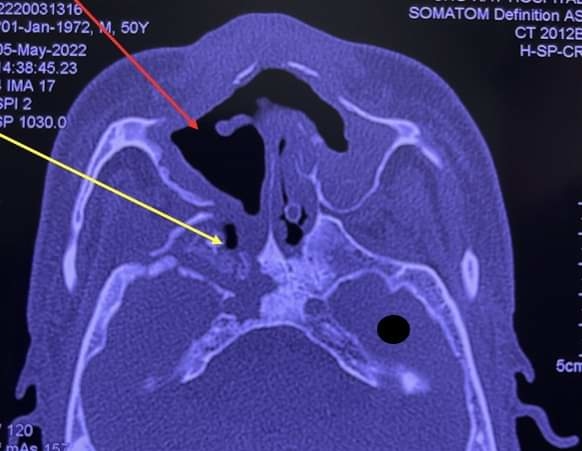

Phim X-quang chụp xương vùng hàm mặt bệnh nhân bị hoại tử. Ảnh: Bệnh viện Chợ Rẫy